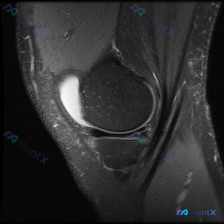

刚看到一份很有代表性的单幅膝关节MRI读片病例,整理了全部信息和分析思路分享给大家。 病例基础信息 本次是膝关节MRI T2序列矢状位单幅影像读片,初始问题是「这张图片里有什么可观察到的异常?」,初始提示提到可能存在半月板异常。 影像学全面观察结果 我们先把所有结构都评估一遍: 1. 骨质与关节面:...